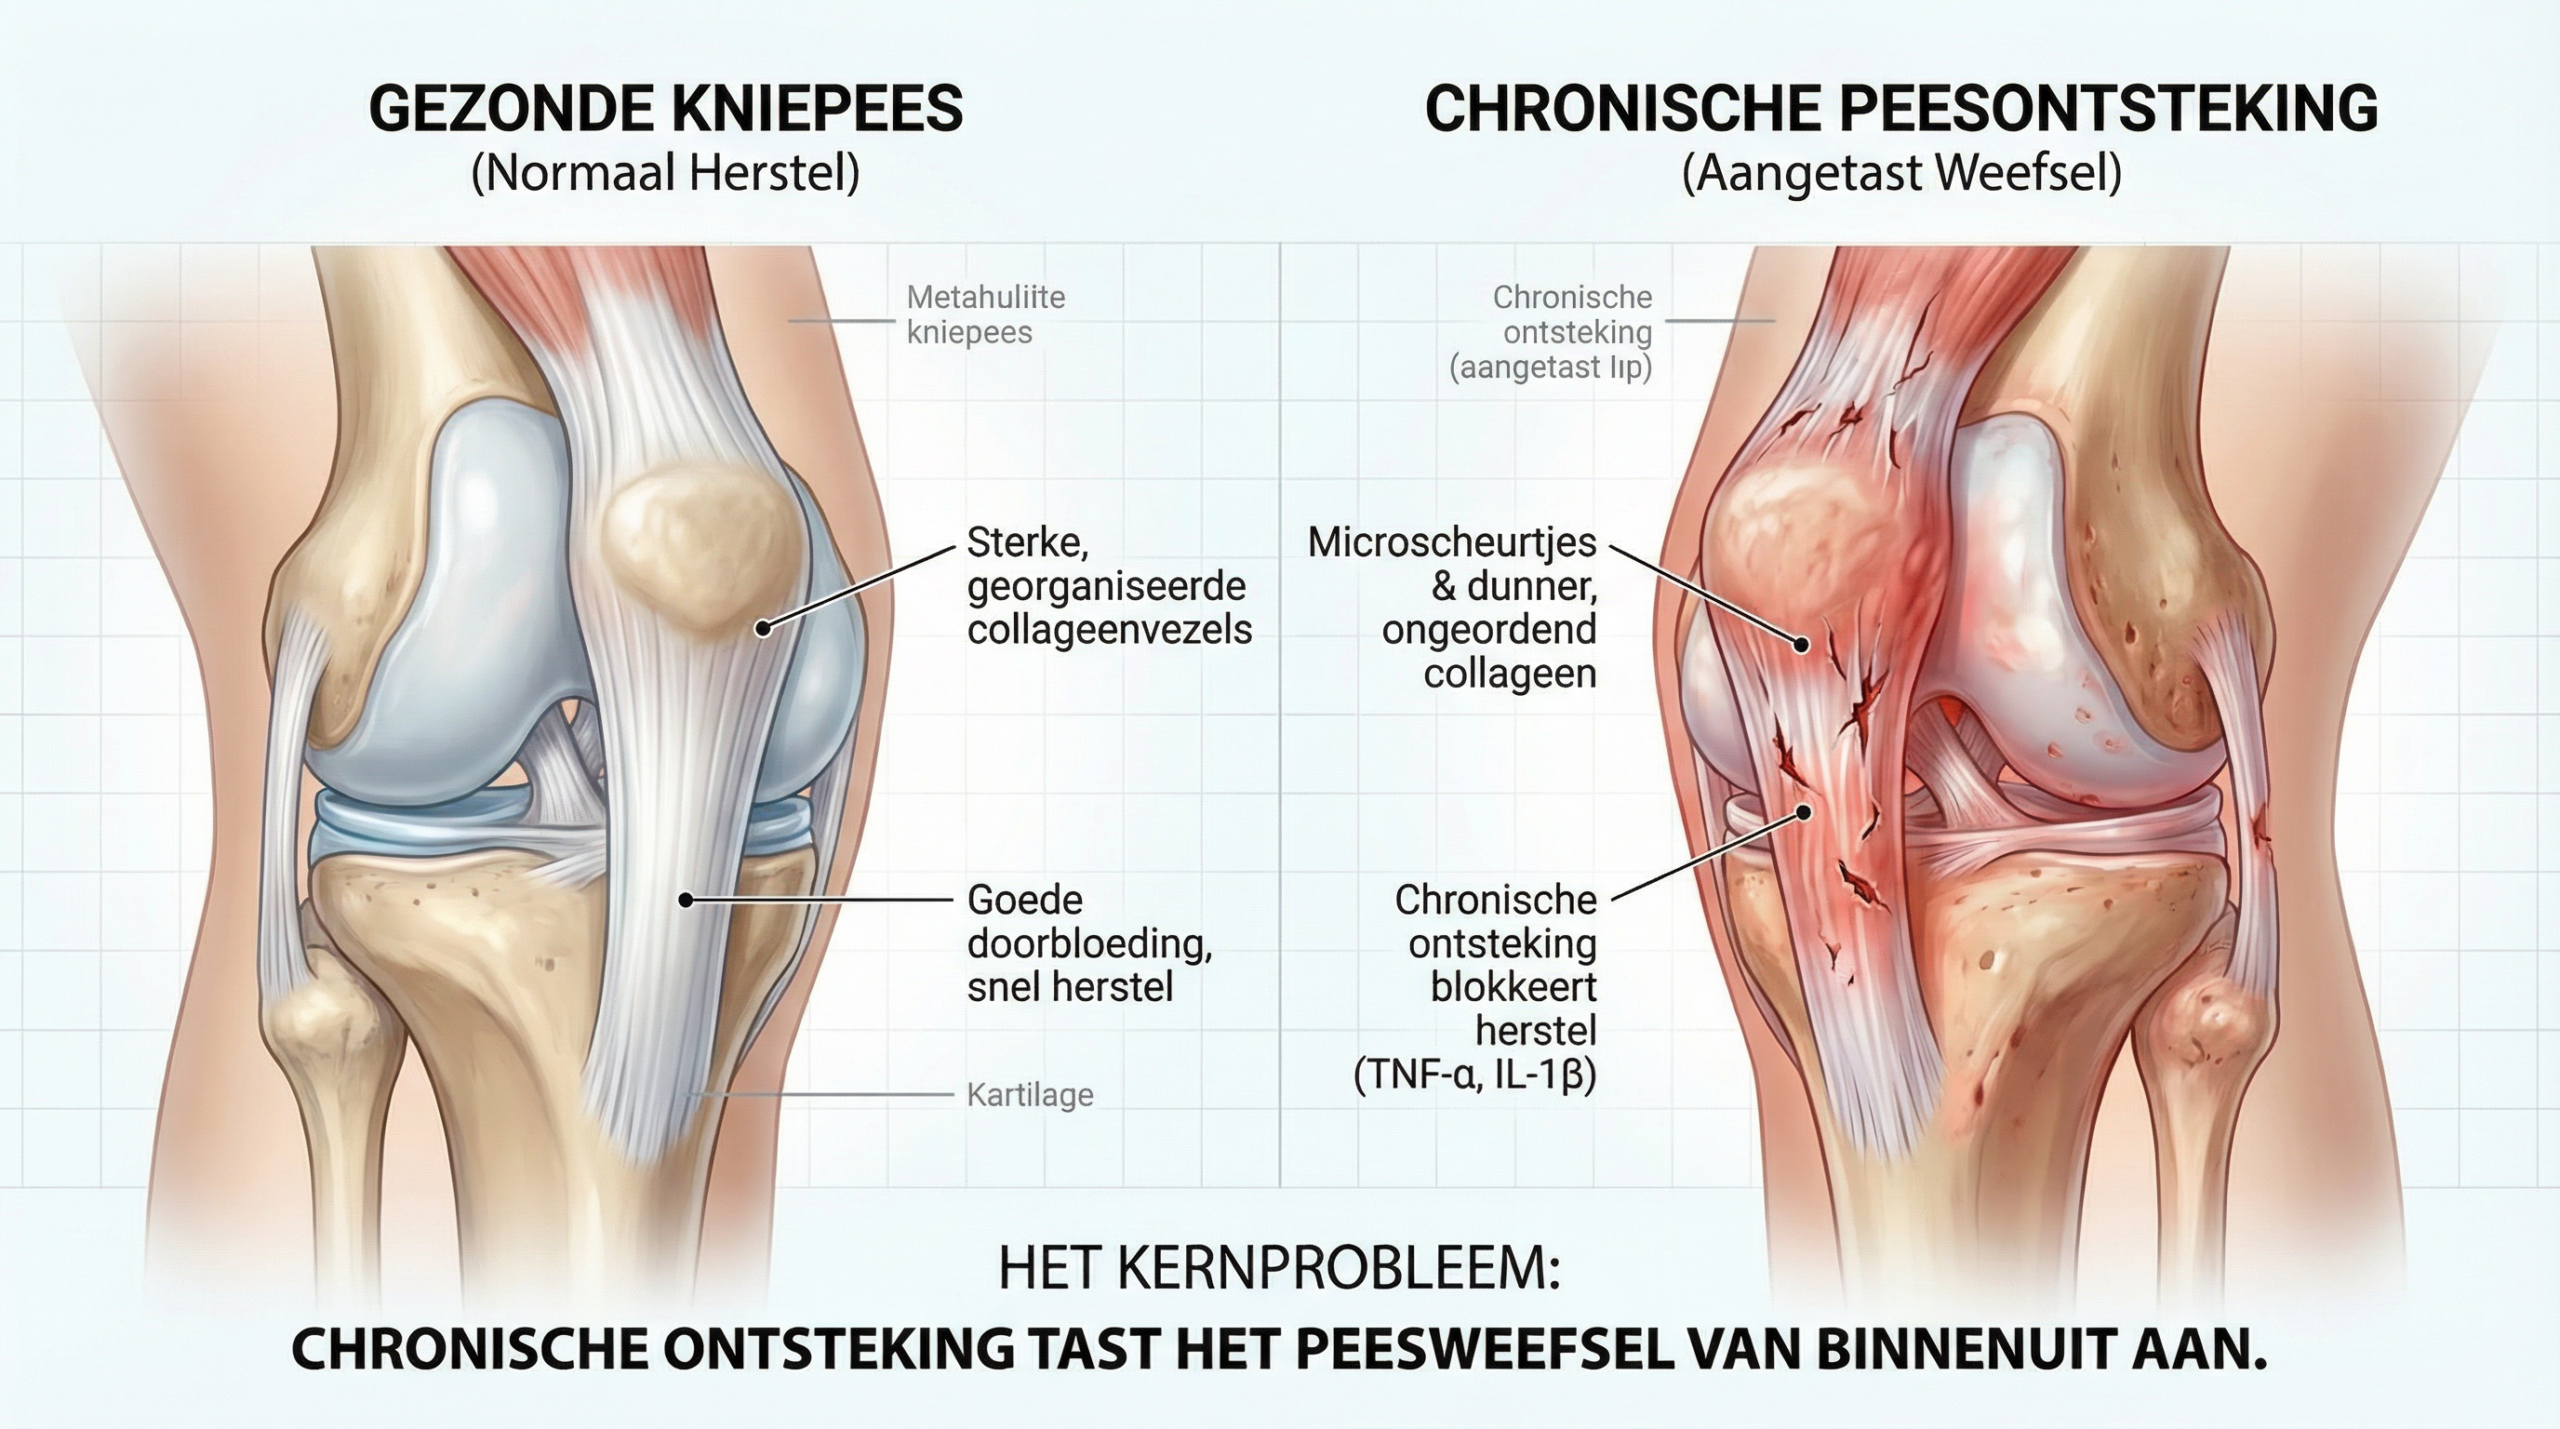

Om het verschil te begrijpen, moeten we eerst begrijpen hoe kniepezen en ontstekingsprocessen in ons lichaam samenwerken.

De patellapees — de kniepees die loopt van de knieschijf naar het scheenbeen — staat bij elke beweging bloot aan enorme krachten.

Ze heeft een beperkte doorbloeding, waardoor herstel na beschadiging aanzienlijk trager verloopt dan bij spierweefsel.

Een gezonde kniepees met intacte collageenstructuur en voldoende doorbloeding herstelt zichzelf na inspanning zonder problemen.

Kijk nu naar een aangetaste kniepees.

Het peesweefsel vertoont microscheurtjes en de collageenvezels zijn dunner en ongeordend geworden — doordat de ontstekingssignalen die normaal voor herstel zorgen, chronisch geactiveerd blijven en het weefsel van binnenuit aantasten.

Het is als een touwbrug met slijtende kabels die bij elke stap en sprong verder onder druk staan.

De eerste scheurtjes zijn onzichtbaar, maar bij elke dag dat de belasting aanhoudt zonder voldoende herstel, groeit de schade — en de pijn wordt progressief erger.

Maar waarom houdt die ontsteking aan?

Wanneer de kniepees herhaaldelijk wordt belast, activeren microscheurtjes pro-inflammatoire cytokinen zoals TNF-α en IL-1β.

Bij jongere mensen herstelt de pees zich nog relatief snel — maar na je veertigste neemt de kwaliteit en het aantal peescellen in de kniepees aantoonbaar af.

De ontstekingssignalen blijven actief, terwijl het herstel achterloopt.

Dit is de hoofdoorzaak van chronische peesontsteking aan de knie.